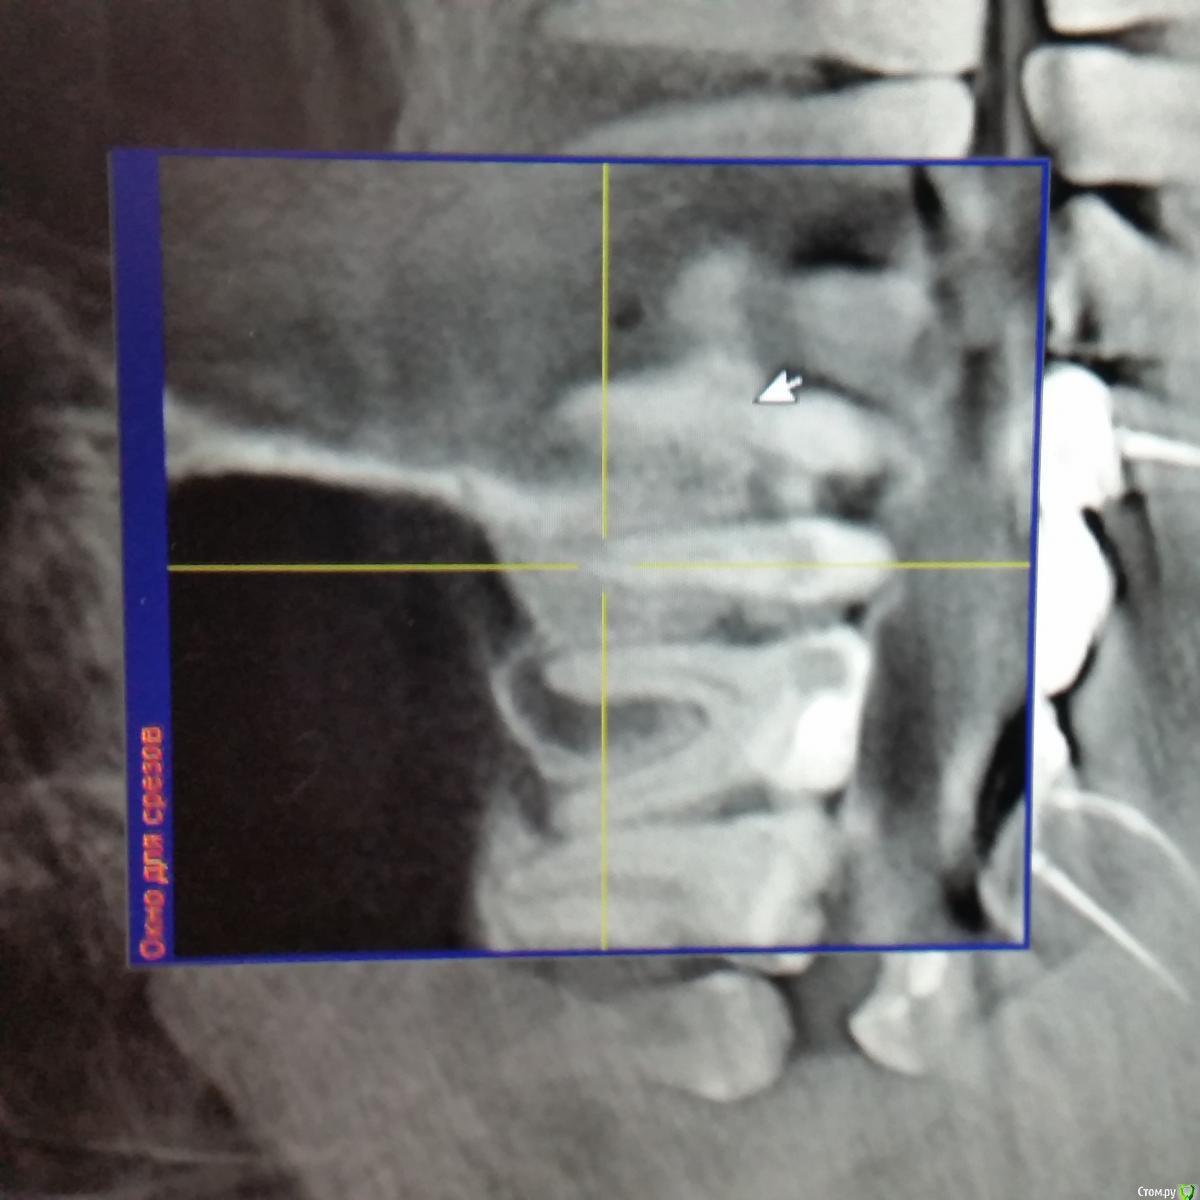

inycik Опубликовано 12 декабря, 2016 Поделиться Опубликовано 12 декабря, 2016 Уважаемые специалисты, помогите советом. Мнения врачей расходятся. Все зубы перелечила. это кт до лечения. Сейчас под временными коронками. Предлагают имплантацию 1.5,2.5 и 4.5 (убрать мост, т.к. 4.6 сильно разрушен). 1.5 удалить и сразу же имплантВопросы. 1. У меня грудной ребенок. Можно ли делать имплантацию2. Нужен ли синус-лифтинг3. Обнаружили проблему в пазухе, что это и может ли повлиять на имплантацию4. Может лучше подождать, чтобы зажило после удаления зубаСсылка на кт https://drive.google.com/file/d/0B7fYoL1llb1HQnEyM0FmOVFxVEU/view?usp=sharing Ссылка на комментарий

Bier Опубликовано 15 декабря, 2016 Поделиться Опубликовано 15 декабря, 2016 с 16м тоже проблема. Скорее всего надо удалять и 15 и 16 и ждать 3-4 мес, потом имплантироваться. Надо еще покрутить КТ, но карман между 16 и 15 очень уж большой.25 с закрытым синуслифтингом, антибиотики не нужны. Ссылка на комментарий